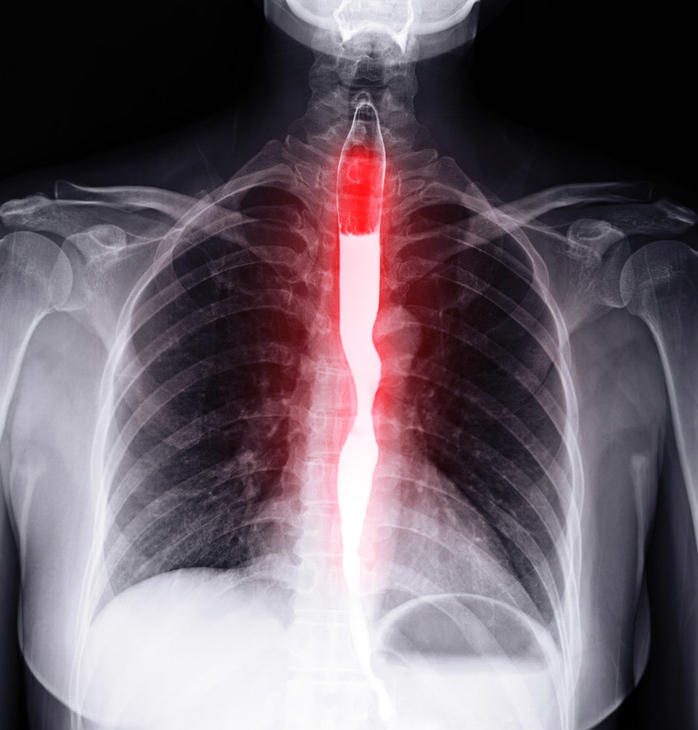

An x-ray of the esophagus shown with barium contrast.

An esophagram using barium contrast shows the esophagus.

Credit: iStock